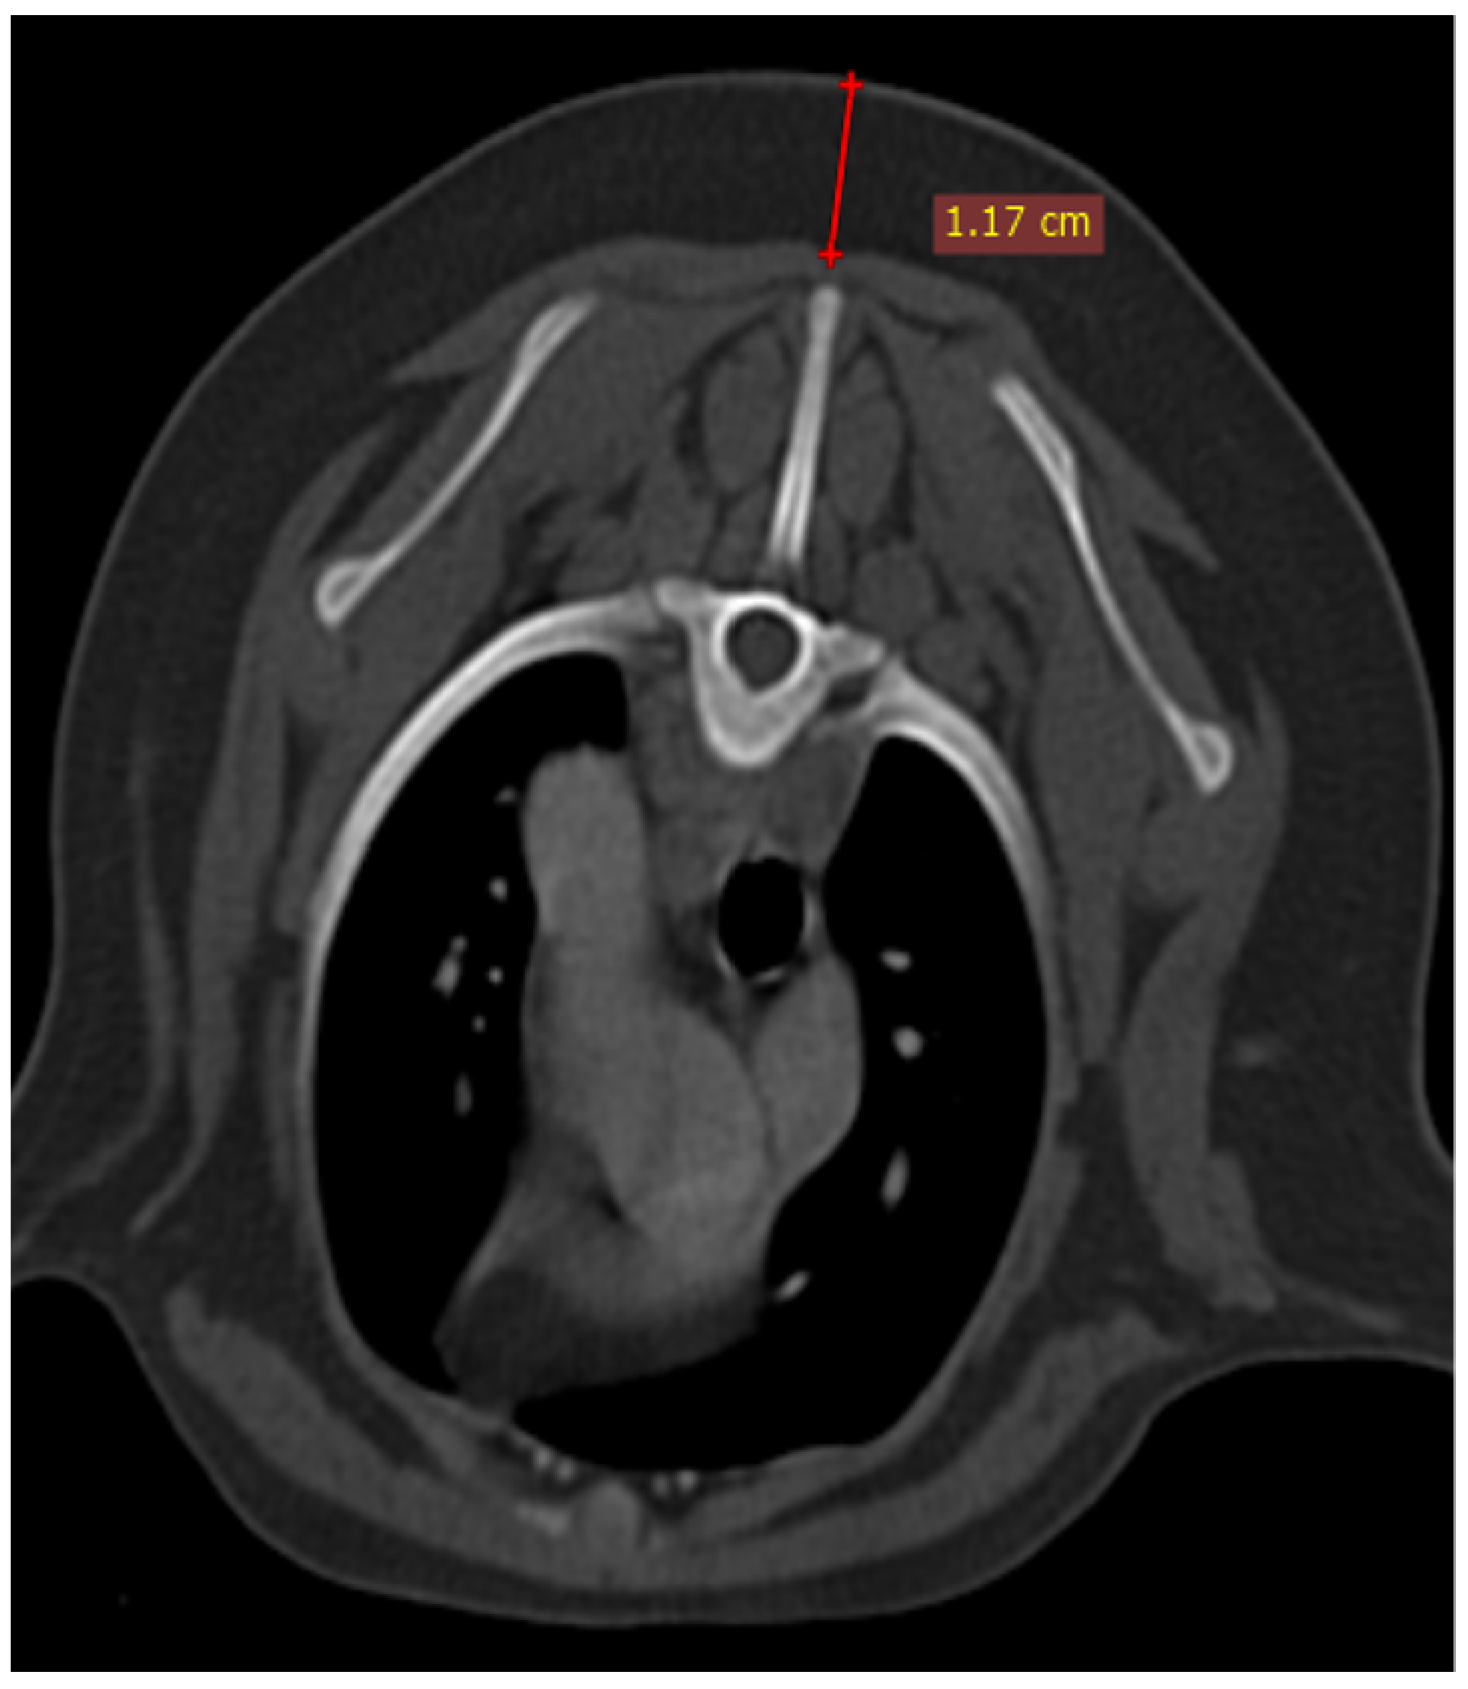

The thymus was evaluated in the first step to determine whether it was visible or not. Non-visible thymus was that with complete degeneration seen with fat attenuation and not distinguishable from mediastinal fat. After that, a grading system for thymic tissue appearance was used based on its predominant component (grade 0: totally fatty replacement of the thymus (non-visible) and could not differentiate from mediastinal fat; grade 1: more than 50% fatty replacement of the thymus; grade 2: more than 50% soft tissue component in the thymus; grade 3: totally soft tissue component in the thymus. After grading the thymus, the attenuation (CT number) of thymic tissue in plain and contrast-enhanced images was measured. For this purpose, a round-shaped region of interest (ROI) with a surface equal to 75 mm2 was considered in the widest part of the organ for large thymus (Figure 1) and a smaller ROI for small thymus. Then pre- and post-contrast Hounsfield Units (HU) were compared for each patient individually and also between groups for evaluating the pattern of attenuation alteration and enhancement alteration.

Figure 1. Illustration of density measurement of thymus in plain (right) and post-contrast (left) CT scan examination in a ROI equal to 75 mm2. These figures belong to a four-month mixed-breed male puppy. The grey dash lines show the grade3 rectangular-shaped midline-position thymus. S: scapula, TV: thoracic vertebra, R: rib, E: esophagus (which is dilated due to general anesthesia), T: trachea, CrVC: cranial vena cava, and asterisk: second sternebra.